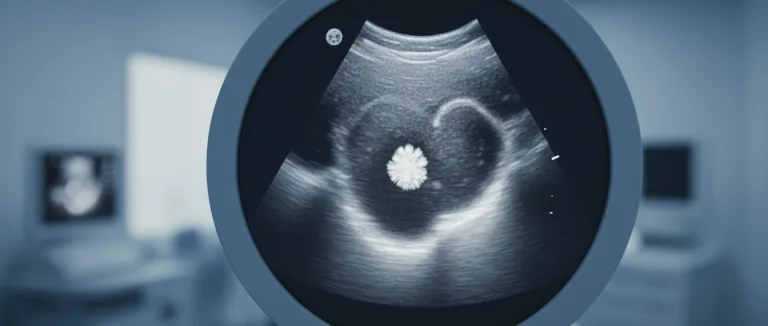

- Ультразвуковое исследование (УЗИ) — первое выбранное средство, позволяющее выявить эхогенные образования в паренхиме почки и в мочеточнике.

| УЗИ | ≈70 % | Без ионизирующего излучения | Ограничена визуализацией мелких камней |